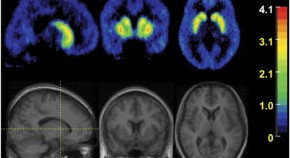

The ovarian hormones oestrogen and progesterone increase breast cancer risk but the cellular mechanisms are unclear. Here it is shown that the size of the mammary stem cell pool in mice is regulated by steroid hormone signalling, although these cells lack the receptors for oestrogen and progesterone. The augmented pool could lead to clonal expansion of a mutated cell, possibly accounting for the increased incidence of breast cancer associated with pregnancy.